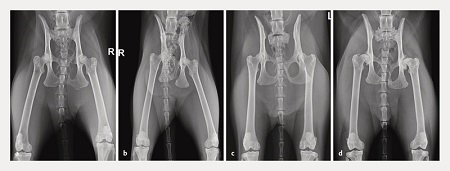

Abbildung 5: Vier Ausprägungen von Luxationen des Iliosakralgelenks (Diastasen).

a Rechtsseitige Diastase mit einem sehr milden Versatz des Iliums gegenüber dem Os sacrum um weniger als 30%. Der Beckenring ist unbeeinträchtigt. Hier sollte die Operationsentscheidung anhand der klinischen Symptomatik getroffen werden. Ist die Schmerzhaftigkeit gut behandelbar und kann der Patient sowohl Last aufnehmen als auch Harn absetzen, ist eine konservative Versorgung zu erwägen.

b Eine rechtsseitige Iliosakralgelenkluxation in Kombination mit einer Fraktur des Scham- und Sitzbeins rechts. Hier kam es zu einer Dislokation des rechten Hemipelvis nach medial. Der Beckenkanal ist eingeengt. Die Indikation zur chirurgischen Versorgung ist damit gegeben. Durch die korrekte Ausrichtung des Iliosakralgelenks mittels Zugschraube kann der Beckenring bereits rekonstruiert werden. Eine Versorgung von Ischium und Pubis ist nicht erforderlich.

c Beidseitige Iliosakralgelenkdiastase. Eine chirurgische Versorgung ist indiziert, weil diese Patienten sonst nur sehr schwer „auf die Beine“ kommen.

d Mittel- bis hochgradig dislozierte Iliosakralgelenkdiastase rechts mit Beteiligung der Beckensymphyse. Durch den starken Versatz des rechten Hemipelvis ist eine Zugschraubenosteosynthese indiziert. Nebenbefundlich bestehen hochgradige Coxarthrosen.